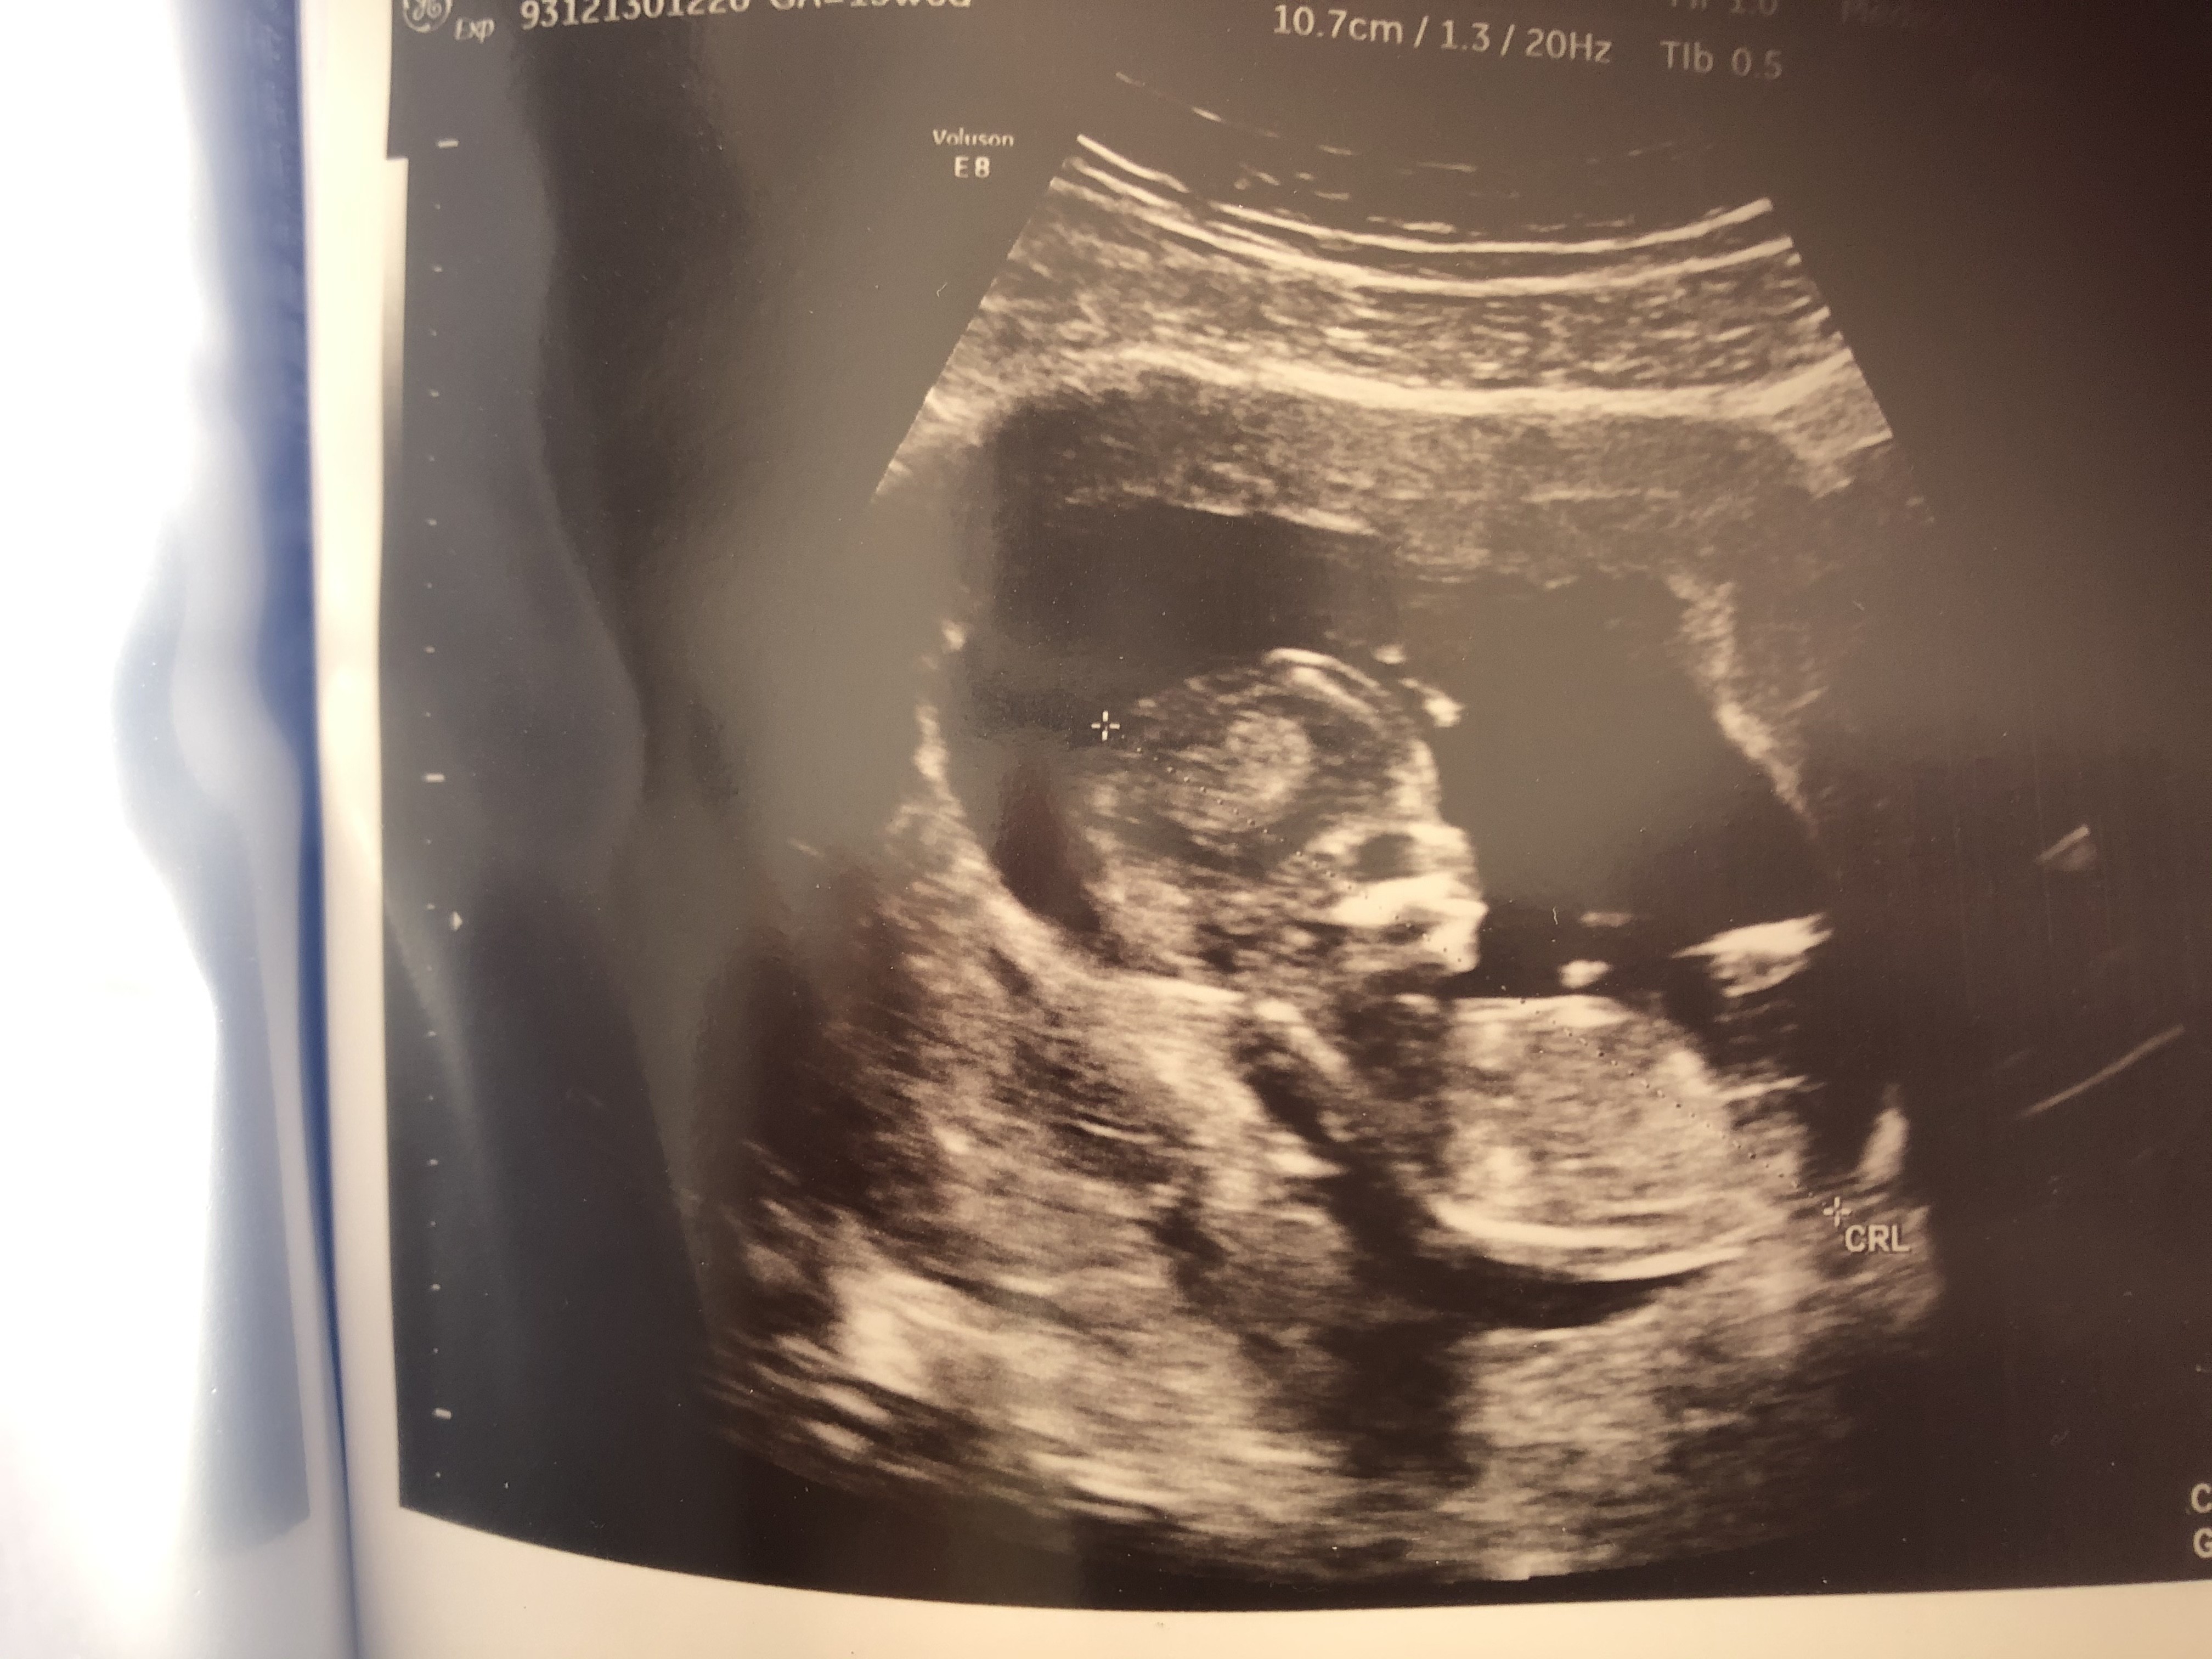

Usg chłopak czy dziewczynka

Witam w 19 tygodniu ciąży dowiedziałam się ze będę miała dziewczynkę w 20 tyg okazało się jednak , że to chłopak. Sama już nie wiem bo na jednym usg widać na pewno dziewuche a na drugim chłopca. Może to pempowina ?? Może ktoś mi pomoże rozwiązać ta zagadkę